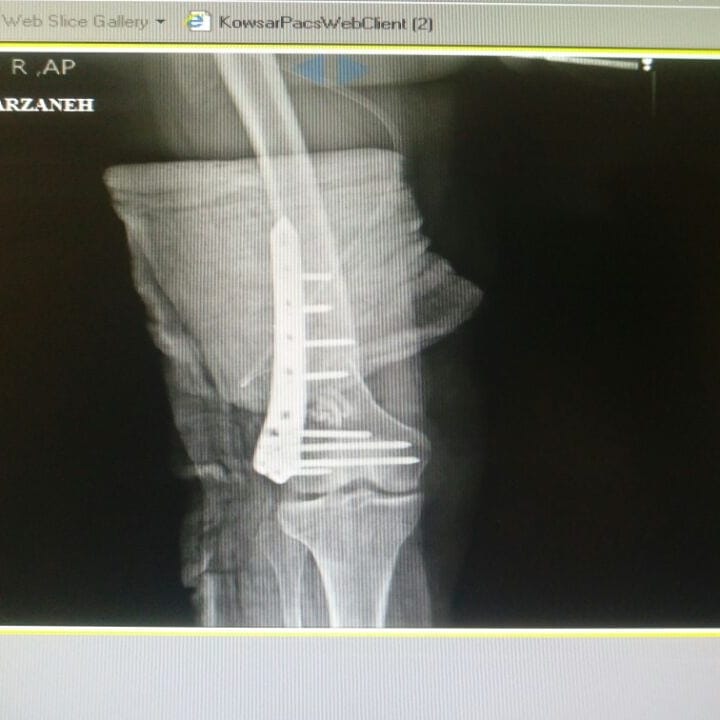

دکتر بسیار عالی و خوش برخوردی هستند استخوان درشت نی و نازک نی ساق پای من شکسته بود جراحی و پیچ و پلاک کردند دستشون شفاس انشالا همیشه موفق باشن من خیلی راضیم